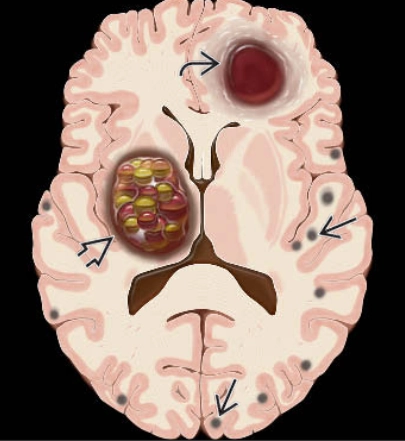

• Bất thường phát triển tĩnh mạch (Developmental Venous Anomaly - DVA)

Bất thường phát triển tĩnh mạch (Developmental Venous Anomaly - DVA)